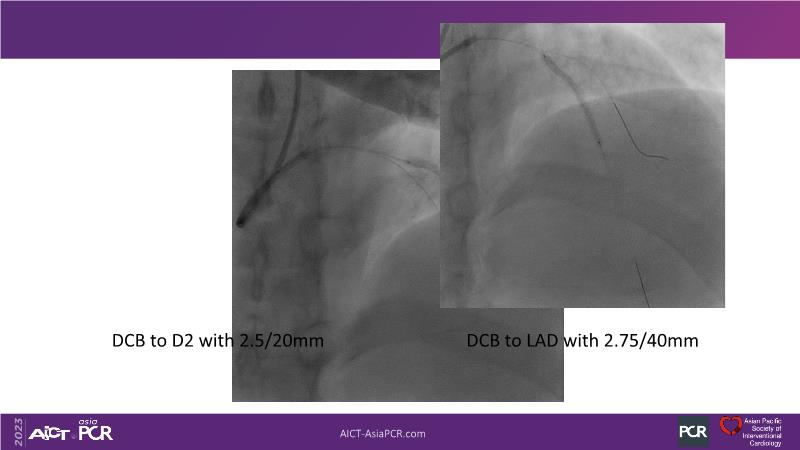

Leave nothing behind: DCB-only PCI strategy - How DCB evidence has changed today's practice?

This session offers an opportunity to stay informed about the recent developments in the International DCB Consensus Group, gain insights into the latest clinical data and real-world experiences related to drug-coated balloon (DCB)-only PCI, understand the safety aspects of DCB in managing complex PCI cases, and participate in an interactive discussion with experts.